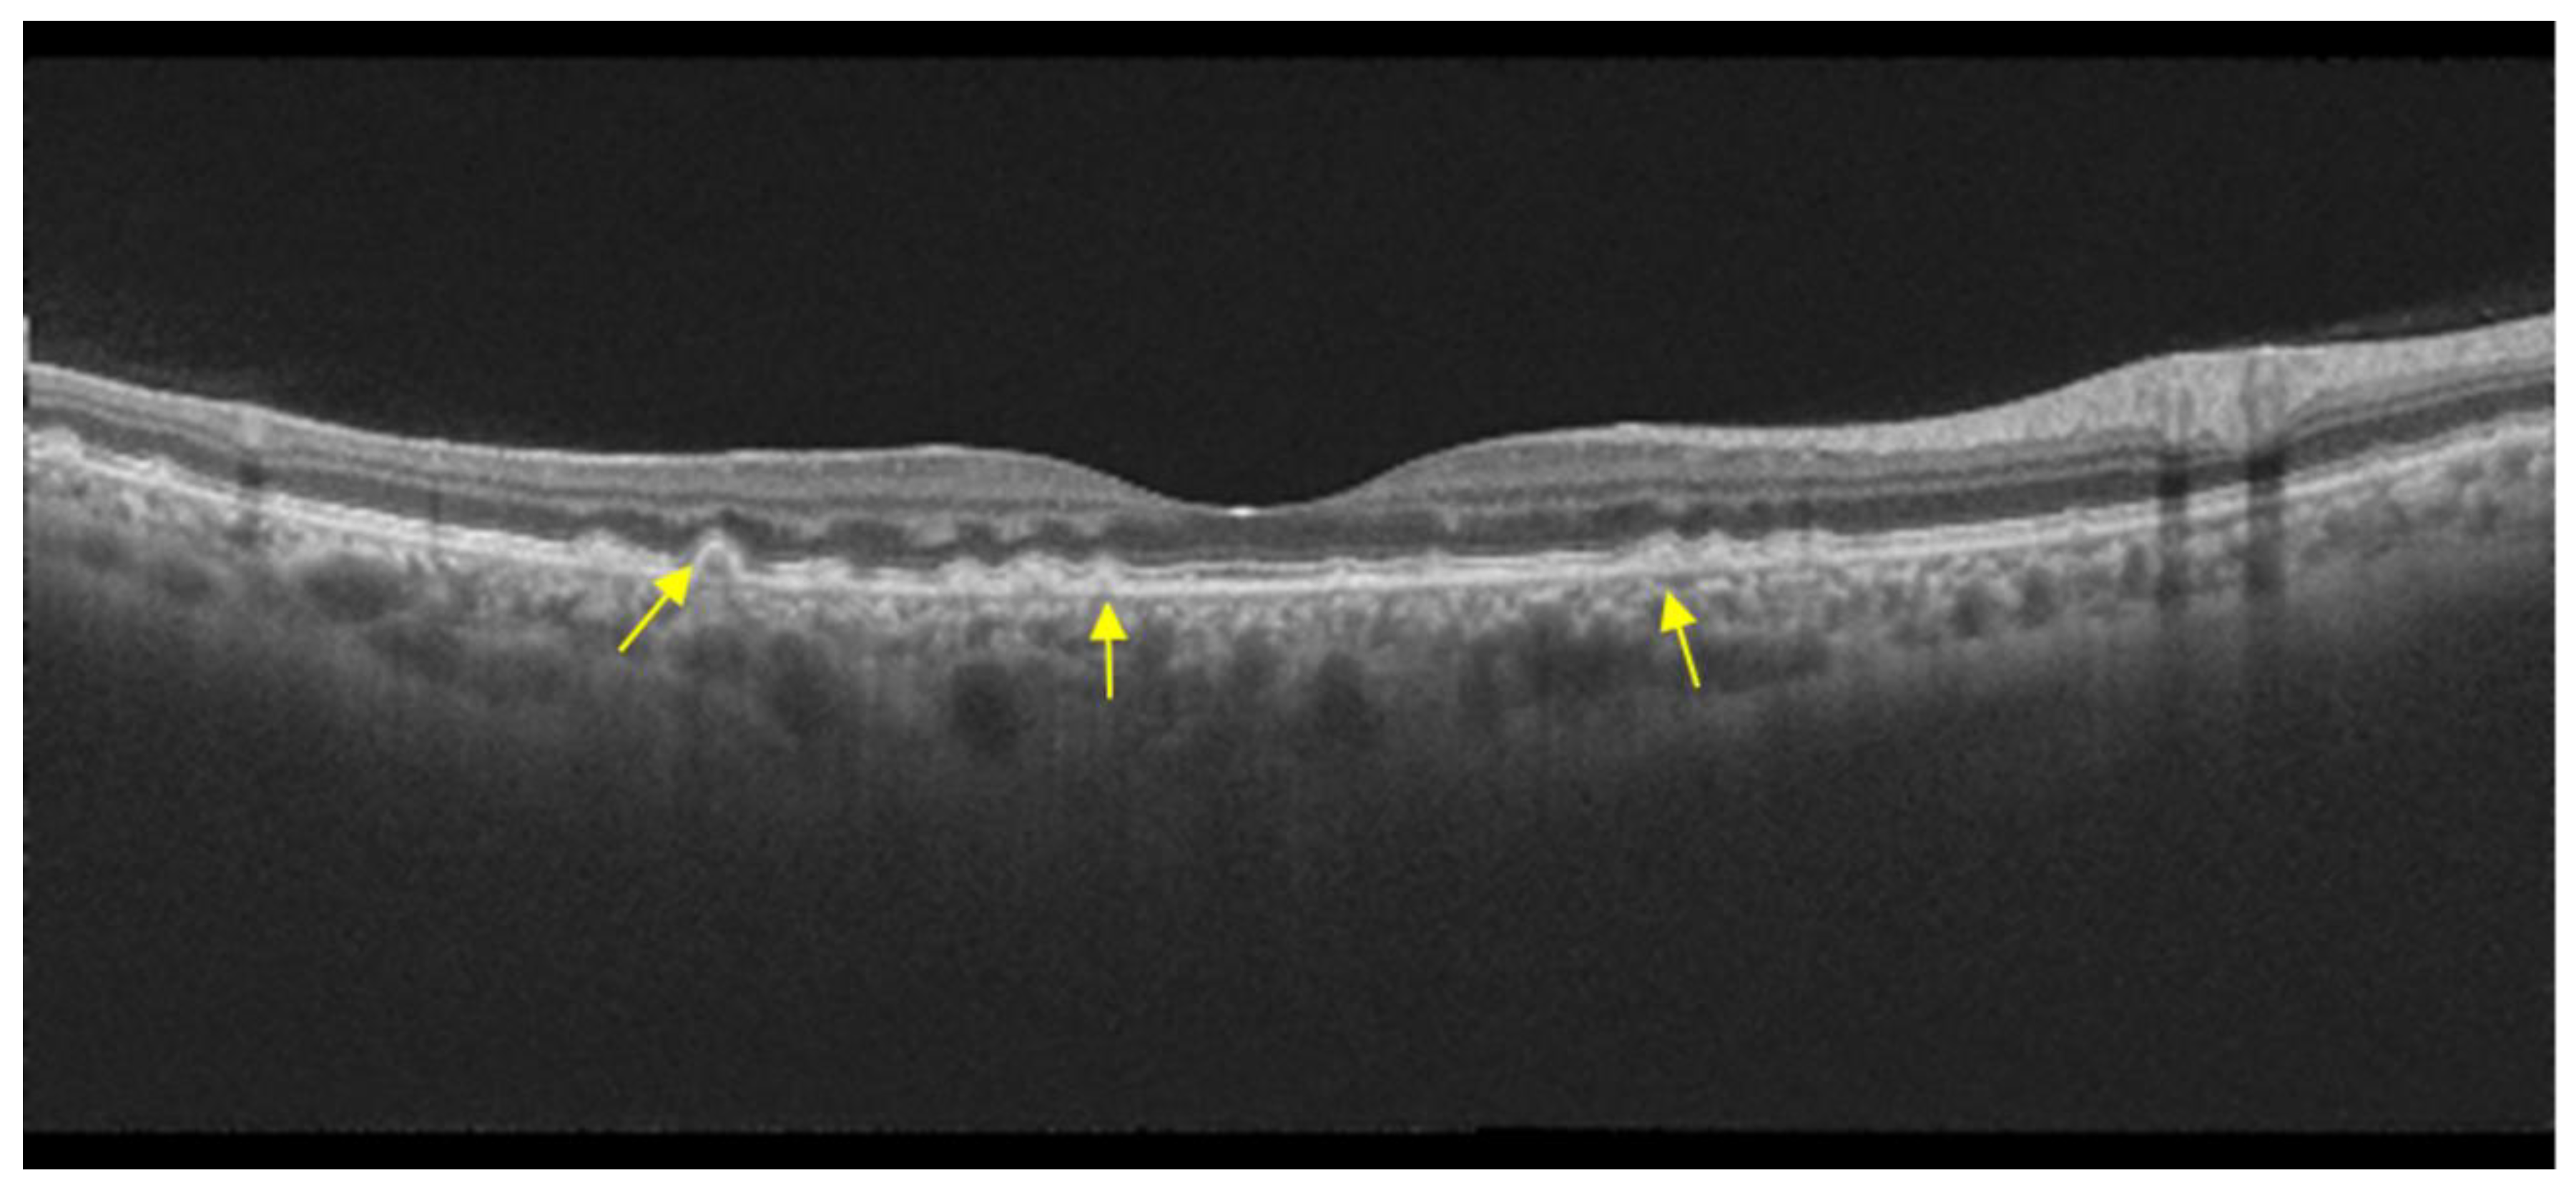

7. Occult Macular Dystrophy

| Occult macular dystrophy |

|